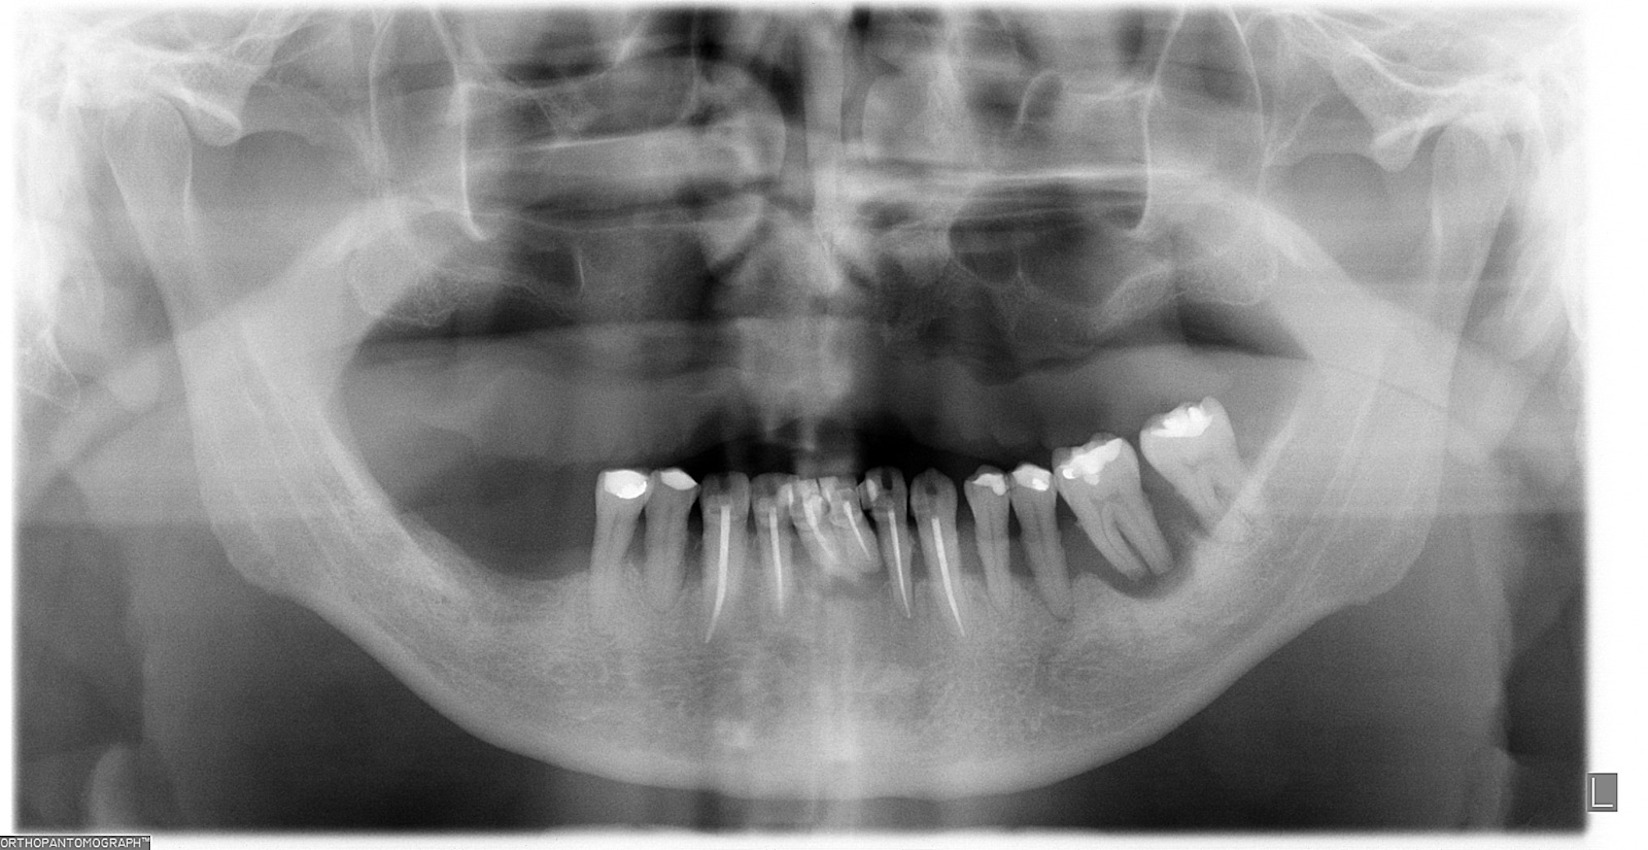

Caso Clínico

¿Sabías que la colocación de implantes dentales ya no es como antes? Gracias a los avances tecnológicos, este procedimiento es ahora más preciso, cómodo y seguro.

Olvídate de las intervenciones invasivas y las largas recuperaciones. En este caso clínico, te mostraremos cómo la tecnología digital se une a la experiencia de nuestros especialistas para lograr resultados sorprendentes.

Planificación de Implantes: Precisión milimétrica

Máxima precisión en implantes dentales: Planificación con tecnología 3D

Planificación digital de implantes: La tecnología al servicio de tu sonrisa